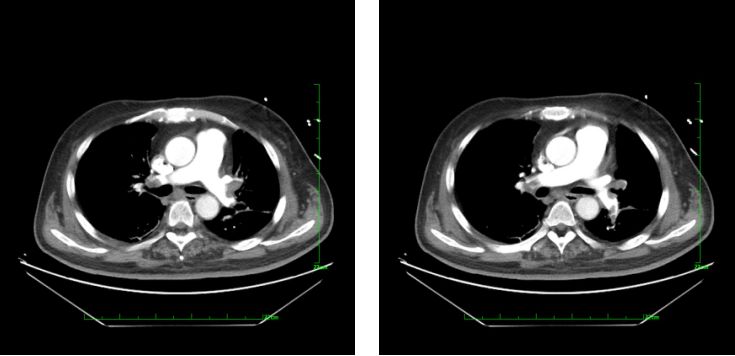

入院后,给予阿司匹林肠溶片100 mg po qd、替格瑞洛 90 mg po bid、瑞舒伐他汀钙片10 mg po qn、依诺肝素40 mg ih q12h、酒石酸美托洛尔25 mg po bid、硝苯地平缓释片30 mg qd。2014年11月4日行肺动脉CTPA示左、右肺动脉主干及其分支肺栓塞(图1)。超声心动图示右心增大,肺动脉频谱异常,注意肺栓塞。

图1.肺动脉CTPA示左、右肺动脉主干及其分支肺栓塞